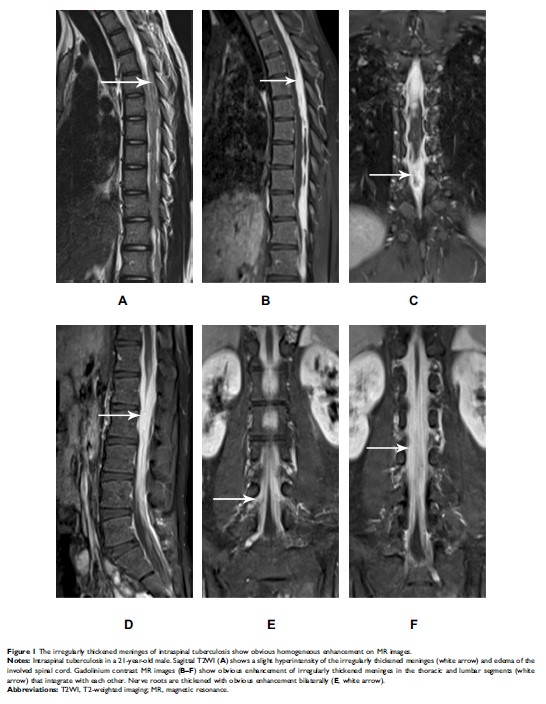

利用磁共振成像鉴别椎管内结核和转移性癌症